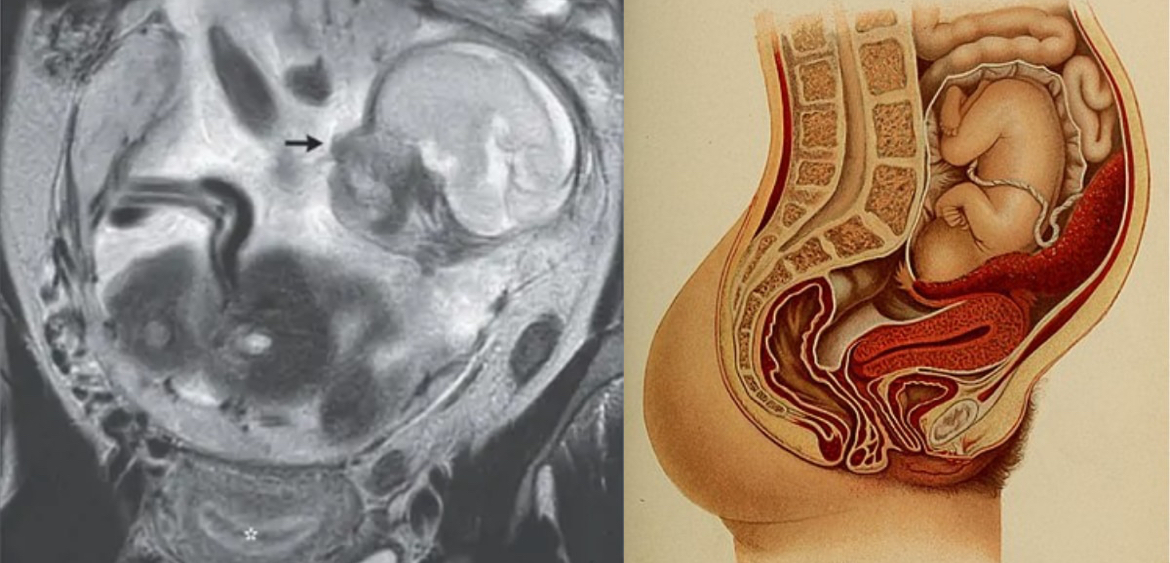

子宮に胎児がいない⁈ 「腹腔で赤ちゃんを妊娠」した極めて稀なケースが報告される ヒトの胎児は決まって、母親の子宮内部である「胎内」で育ちます。

しかし仏レユニオン大学病院センター(Le CHU de La Réunion)は最近、あるフランス人女性が子宮の外側である「腹腔(ふくこう)」の中で赤ちゃんを妊娠するという極めて稀なケースを報告しました。

腹腔は胃や腸といった大事な臓器を収めているデリケートな場所で、ここで胎児が発育することは普通ありえませんし、母子ともに非常に危険です。